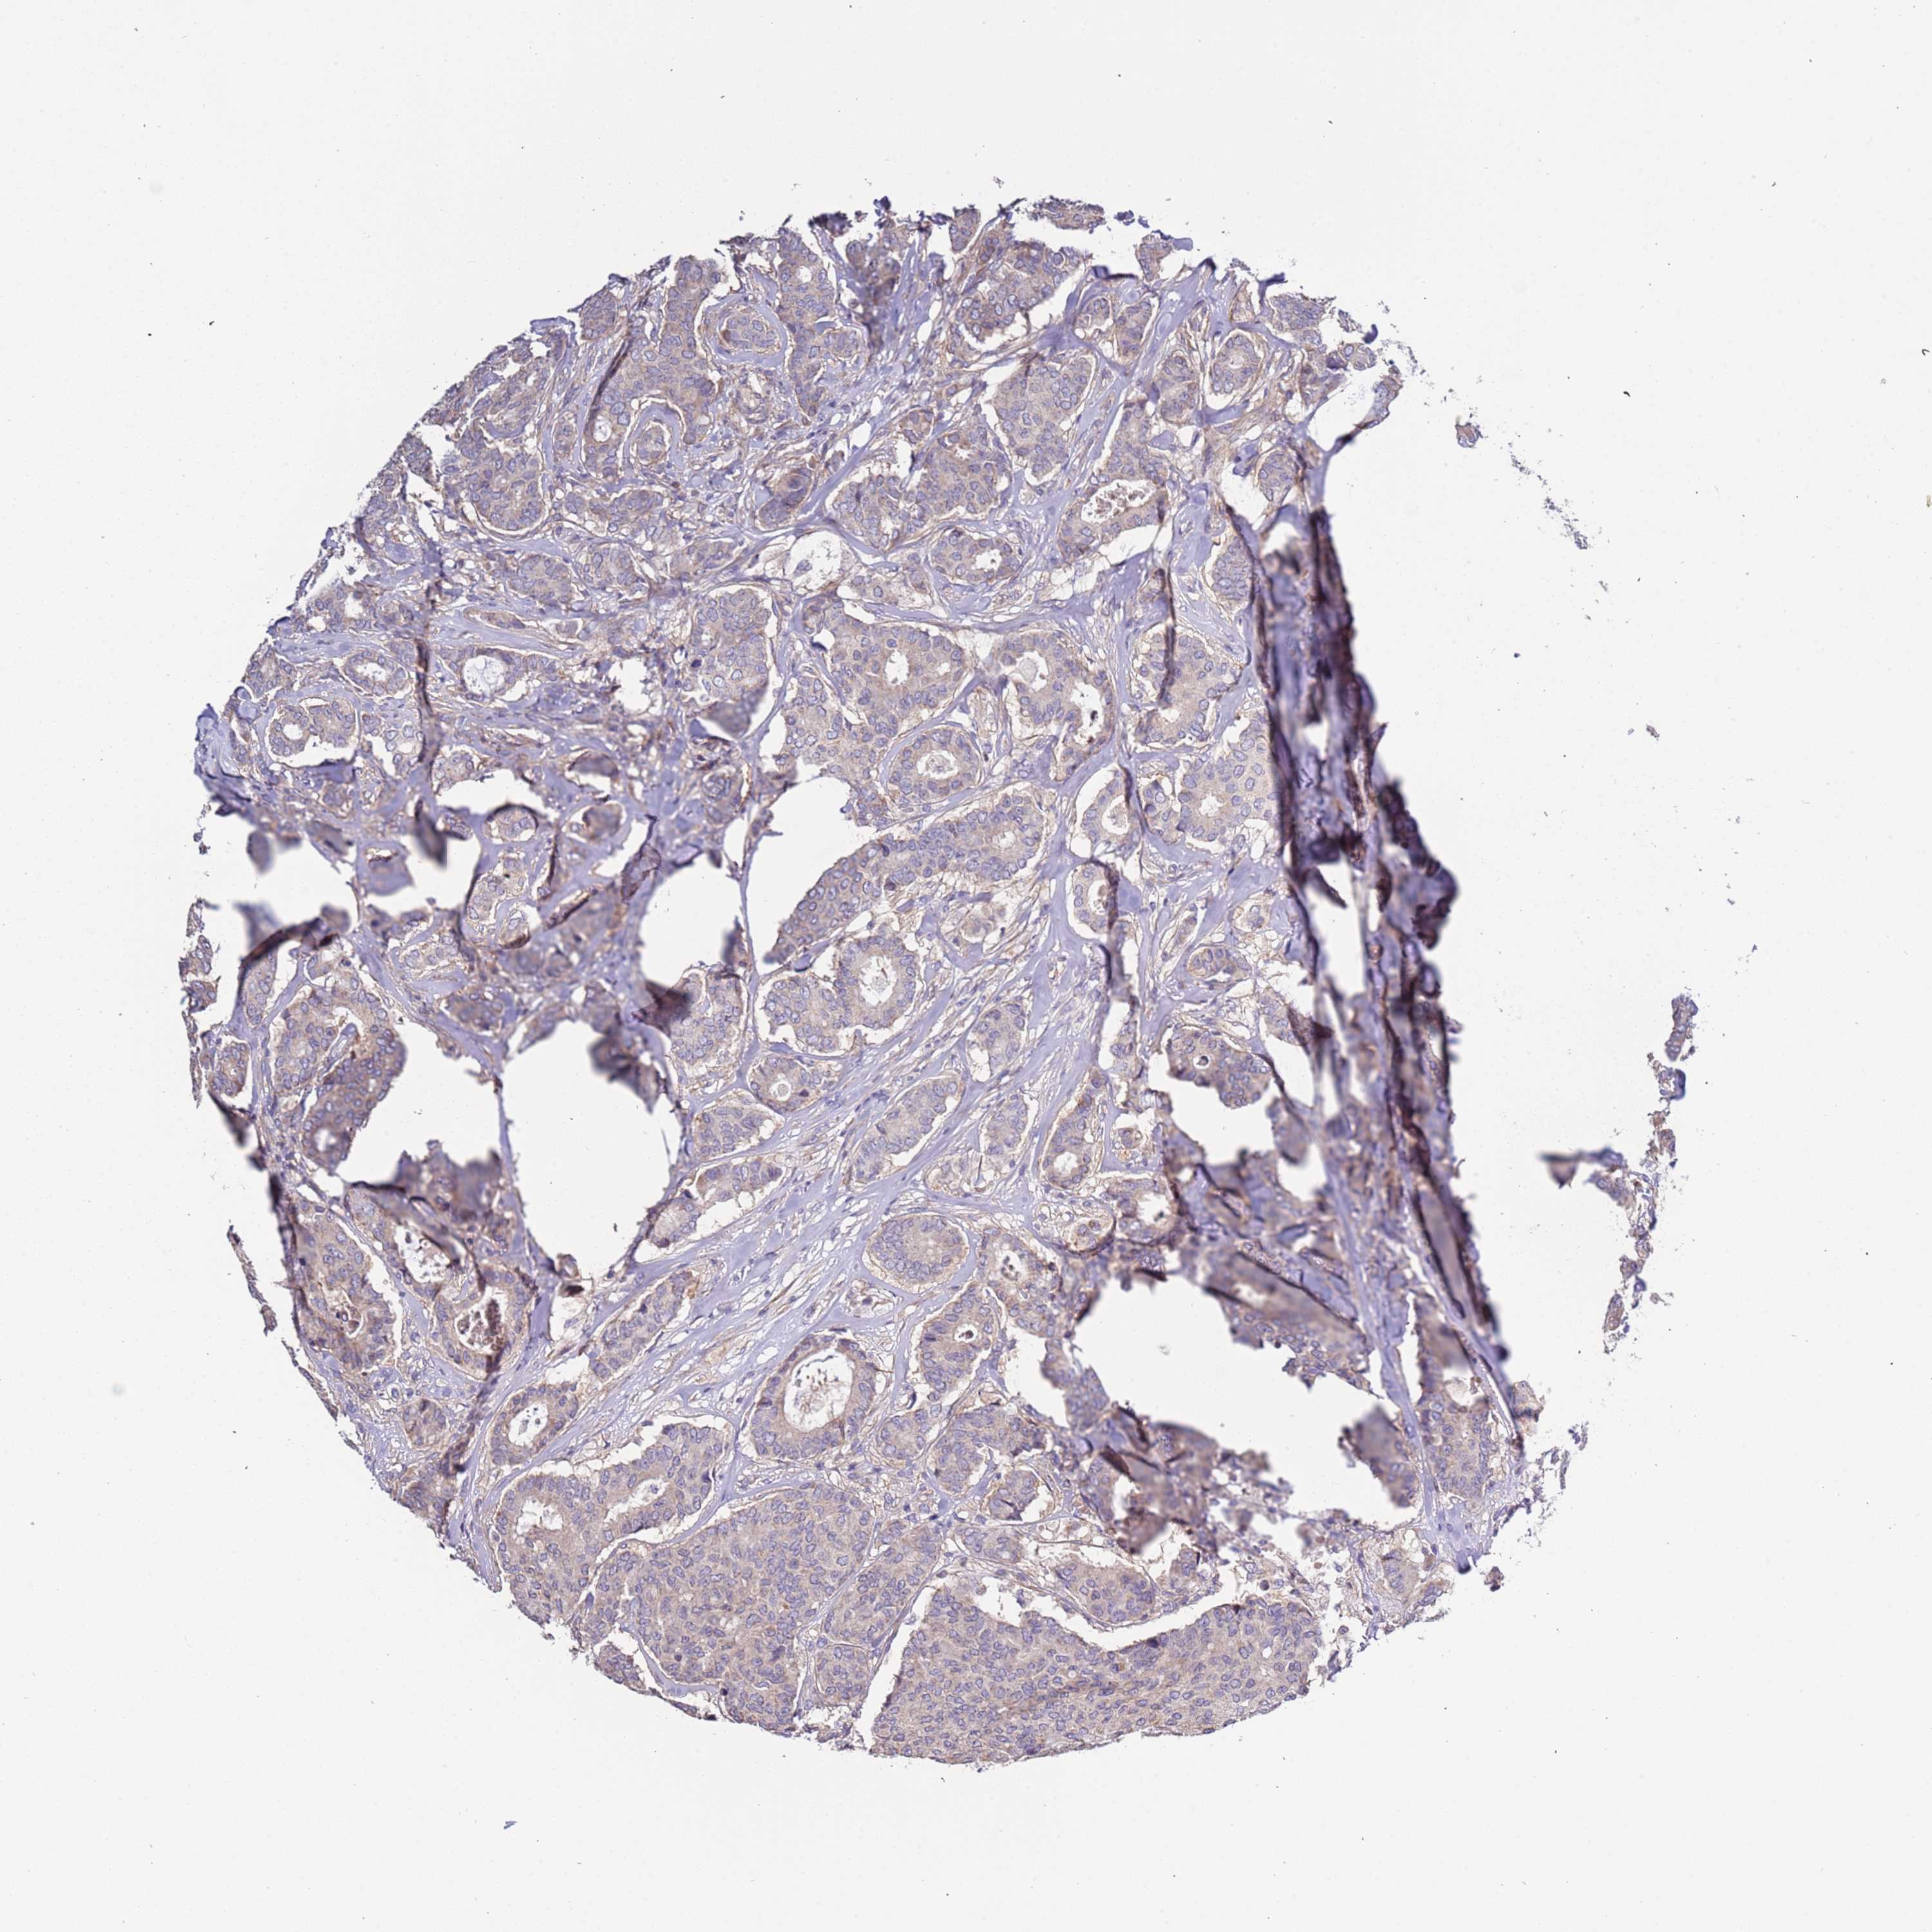

CANCER BREAST CANCER Show tissue menu

BRCA TCGA BRCA VALIDATION PROTEIN EXPRESSION

ANTIBODIES

AND

VALIDATION